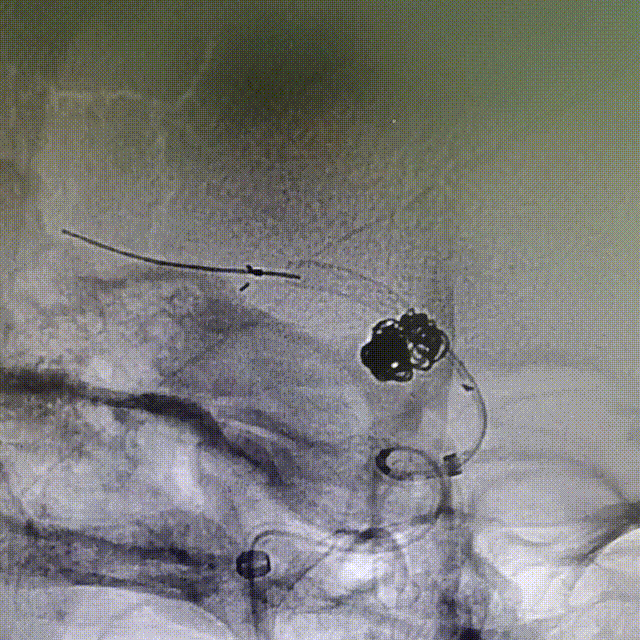

Synchro2微导丝成袢穿越Atlas支架内“真腔”,到达远端;XT-17微导管头端塑形“小半径”J型弯,沿Synchro2微导丝进入Atlas支架内远端;回撤Synchro2微导丝,配合XT-17微导管超选Atlas支架网孔。

XT-17微导管穿网孔进入瘤腔;A为XT17远端Mark点,B为XT17近端Mark点。

XT-17微导管依次填入Target 5-15/4-8/2-6/2-6/1.5-3,造影确认填塞效果基本满意。

用导丝成袢带XT-27支架导管到位时卡住辅助支架近端Mark,前推XT-27增张后透视下发现辅助支架近端少了一个Mark点,疑似支架近端钢梁被XT-27推得内翻。XT-27顺利到位,预置在大脑中M2。